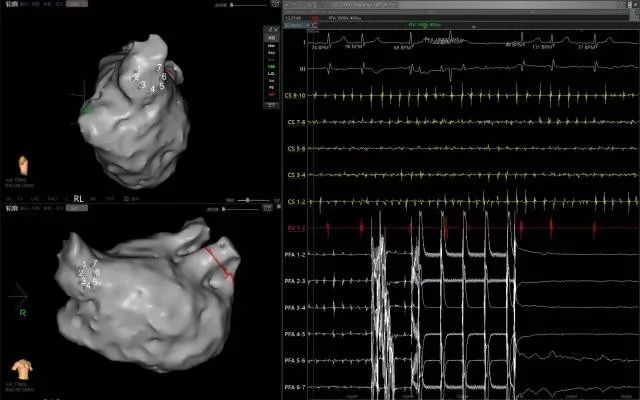

PFA是一种创新且有前景的微创、安全和高效的新兴治疗方法,通过瞬时的高电压脉冲电场直接作用于心肌细胞,以不可逆电穿孔机制消融心脏组织,有效的隔绝异常激动及异位传导路径,从而恢复正常心律。PFA具有独特的消融组织选择性、消融时间极短、无热损伤炎性水肿和附带周围组织损伤并发症等特点,是现有技术中针对心律失常更理想的消融手段,可大大减少因传统消融存在手术并发症风险及消融不足导致房颤复发的风险。与传统的射频导管消融或冷冻球囊消融相比,脉冲电场消融手术具有更加安全、消融效率高、并发症少等诸多优点,彻底改变了房颤治疗的格局,为房颤患者带来更好的治疗方案,带来更多治愈的希望。

此次手术患者均为持续性房颤患者,由延安大学咸阳医院吴栋梁院长、心律失常专家刘雄涛副院长带领介入团队开展,安全高效、圆满完成手术,手术过程患者全程清醒,术中自诉感觉良好,无痛苦感受。术后患者的心律恢复并维持了窦律,目前恢复情况良好,无任何并发症出现。